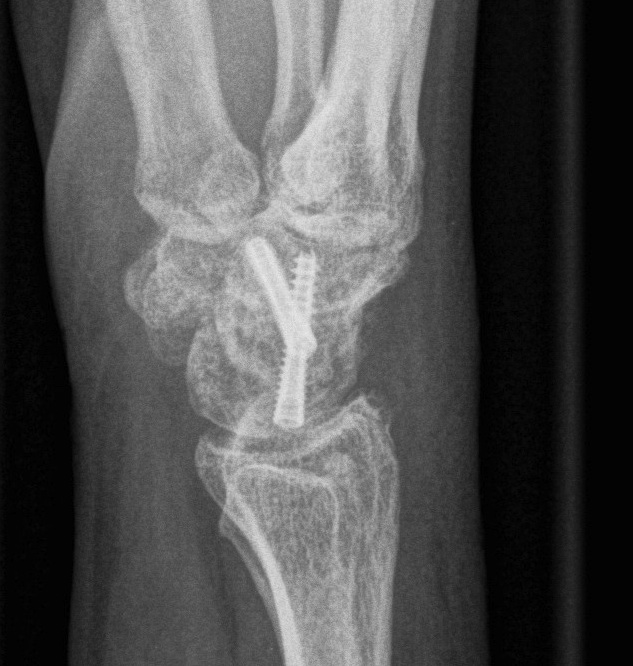

Fixation

- headless compression screws

- dorsal circular plate

- K wires

Scaphoidectomy & Four Corner Fusion

Technique

- resect scaphoid

- denude surfaces of lunate / capitate / hamate / triquetrum

- use good quality BG from distal radius

- must reduce the lunate out of extension or will impinge dorsally